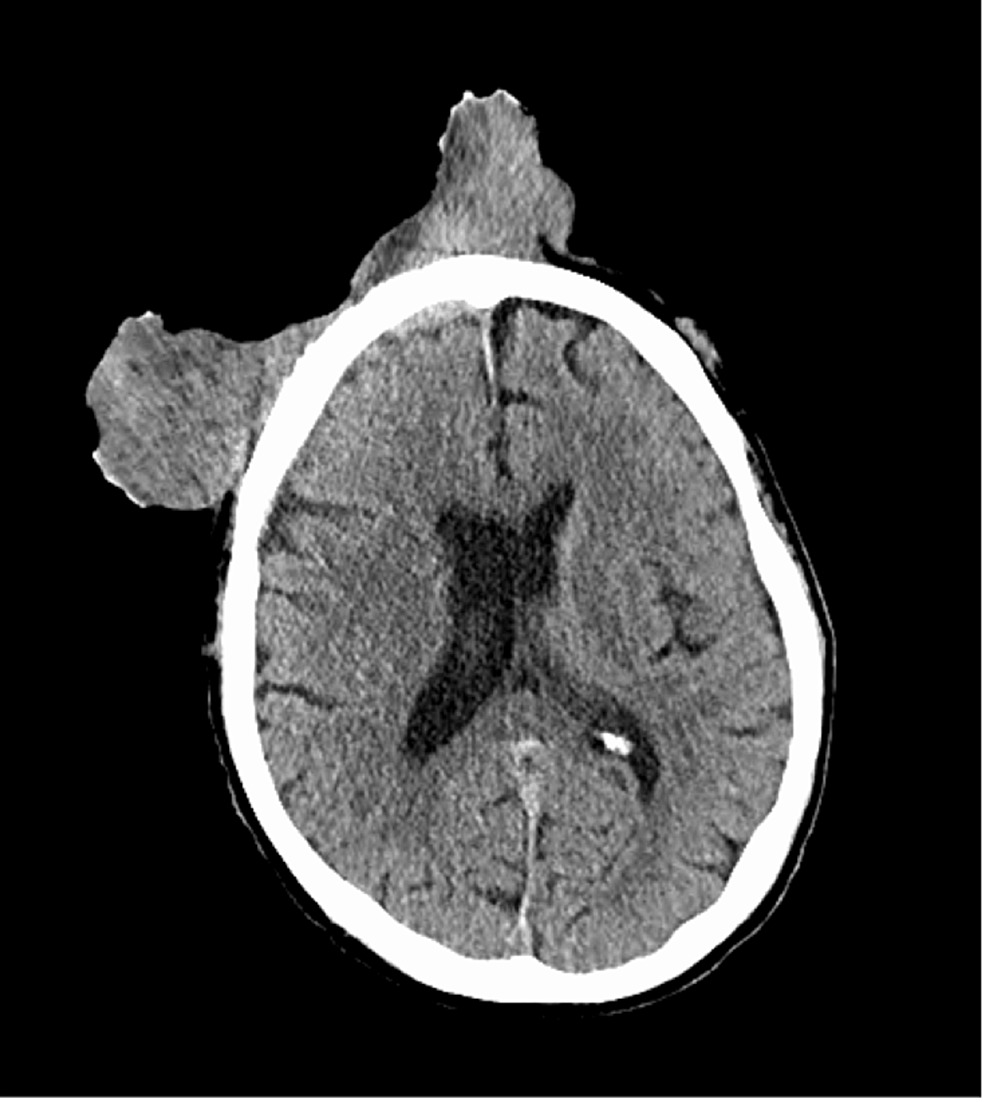

重度の貧血を訴えて病院にやってきた65歳の男性の画像。

男性の顔には扁平上皮癌による大きな腫瘤があり、悪臭を放っていた。男性は自分の額に小さなしこりがあることに気づき、それが少しずつ大きくなっていったため病院の診察を受けようとしたものの、新型コロナウイルス感染症のパンデミック中で手術を延期され続けていた。

男性は自宅で腫瘤を自分で切除しようと試みたが、うまくいかず、症状はさらに悪化。この状態になってようやく病院で検査することができた。